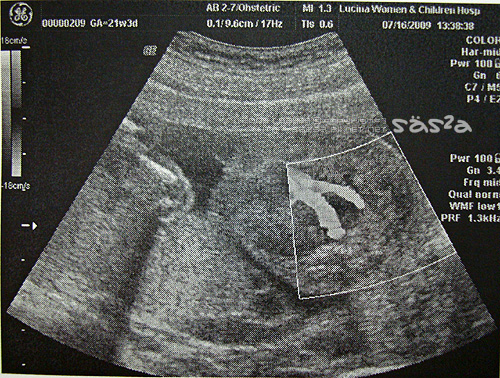

當然我們也看到傳說中的彩色影像,醫生介紹著臍帶血的流動,兩條呈現一個Y字型,紅色的血液正流動著,好神奇。最後唐氏症的檢查報告出爐啦!醫生說照一般產檢就可以了。我想...這是正常的意思嗎?柚子泥目前21W4D,體重345G,比起同周數的400G少上一些,醫生說在正常值內,還有很長的時間可以慢慢長,多吃點甜也可以。柚子泥一定知道媽咪不想要他太大隻,怕不好生XDDD